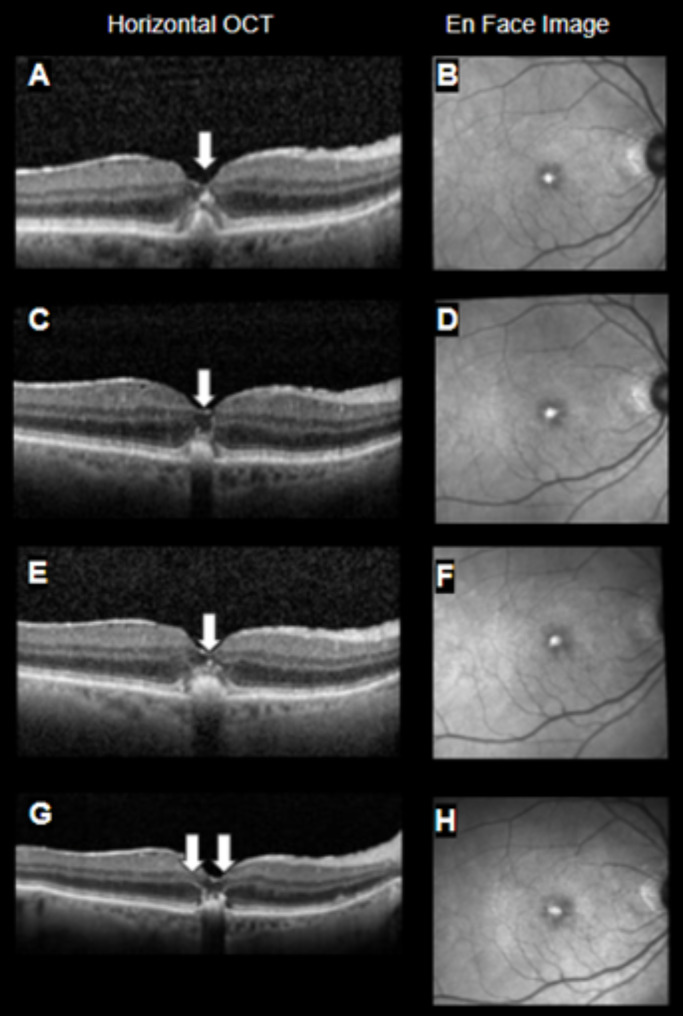

Purpose: To determine if eyes with the foveal crack sign (FCS) in macular pattern dystrophy (MPD) progress to macular holes, and if FCS occurs in the context of hyperreflective foci (HRF) that do not reach the threshold of FCS.

Patients and methods: A retrospective chart review of eyes with MPD was conducted in the Atrium Health Wake Forest Baptist medical system. 56 eyes from 32 patients identified as having macular pattern dystrophy were identified. Demographic data were collected from charts and spectral domain optical coherence tomographs (SD-OCTs) were analyzed.

Results: 8 eyes from 6 patients were found to have an FCS-positive OCT at any point at or following their initial diagnosis of MPD. One eye developed a full-thickness stage 4 macular hole during follow-up. There was no significant difference in macular hole development between MPD eyes with and without FCS (p =.1429). There was a significant difference in FCS development between MPD eyes with and without HRF (p =.0063).

Conclusions: The data did not show a significant difference in macular hole generation between eyes with and without FCS, unlike the situation of FCS in eyes post vitrectomy for retinal detachment repair. The significant association between HRF and FCS suggests that the two signs may have a related pathophysiology and may represent different stages in a common degenerative process. Further work is needed to better characterize the relationship of FCS and HRF and to determine if FCS has different implications in the different clinical contexts in which it appears.